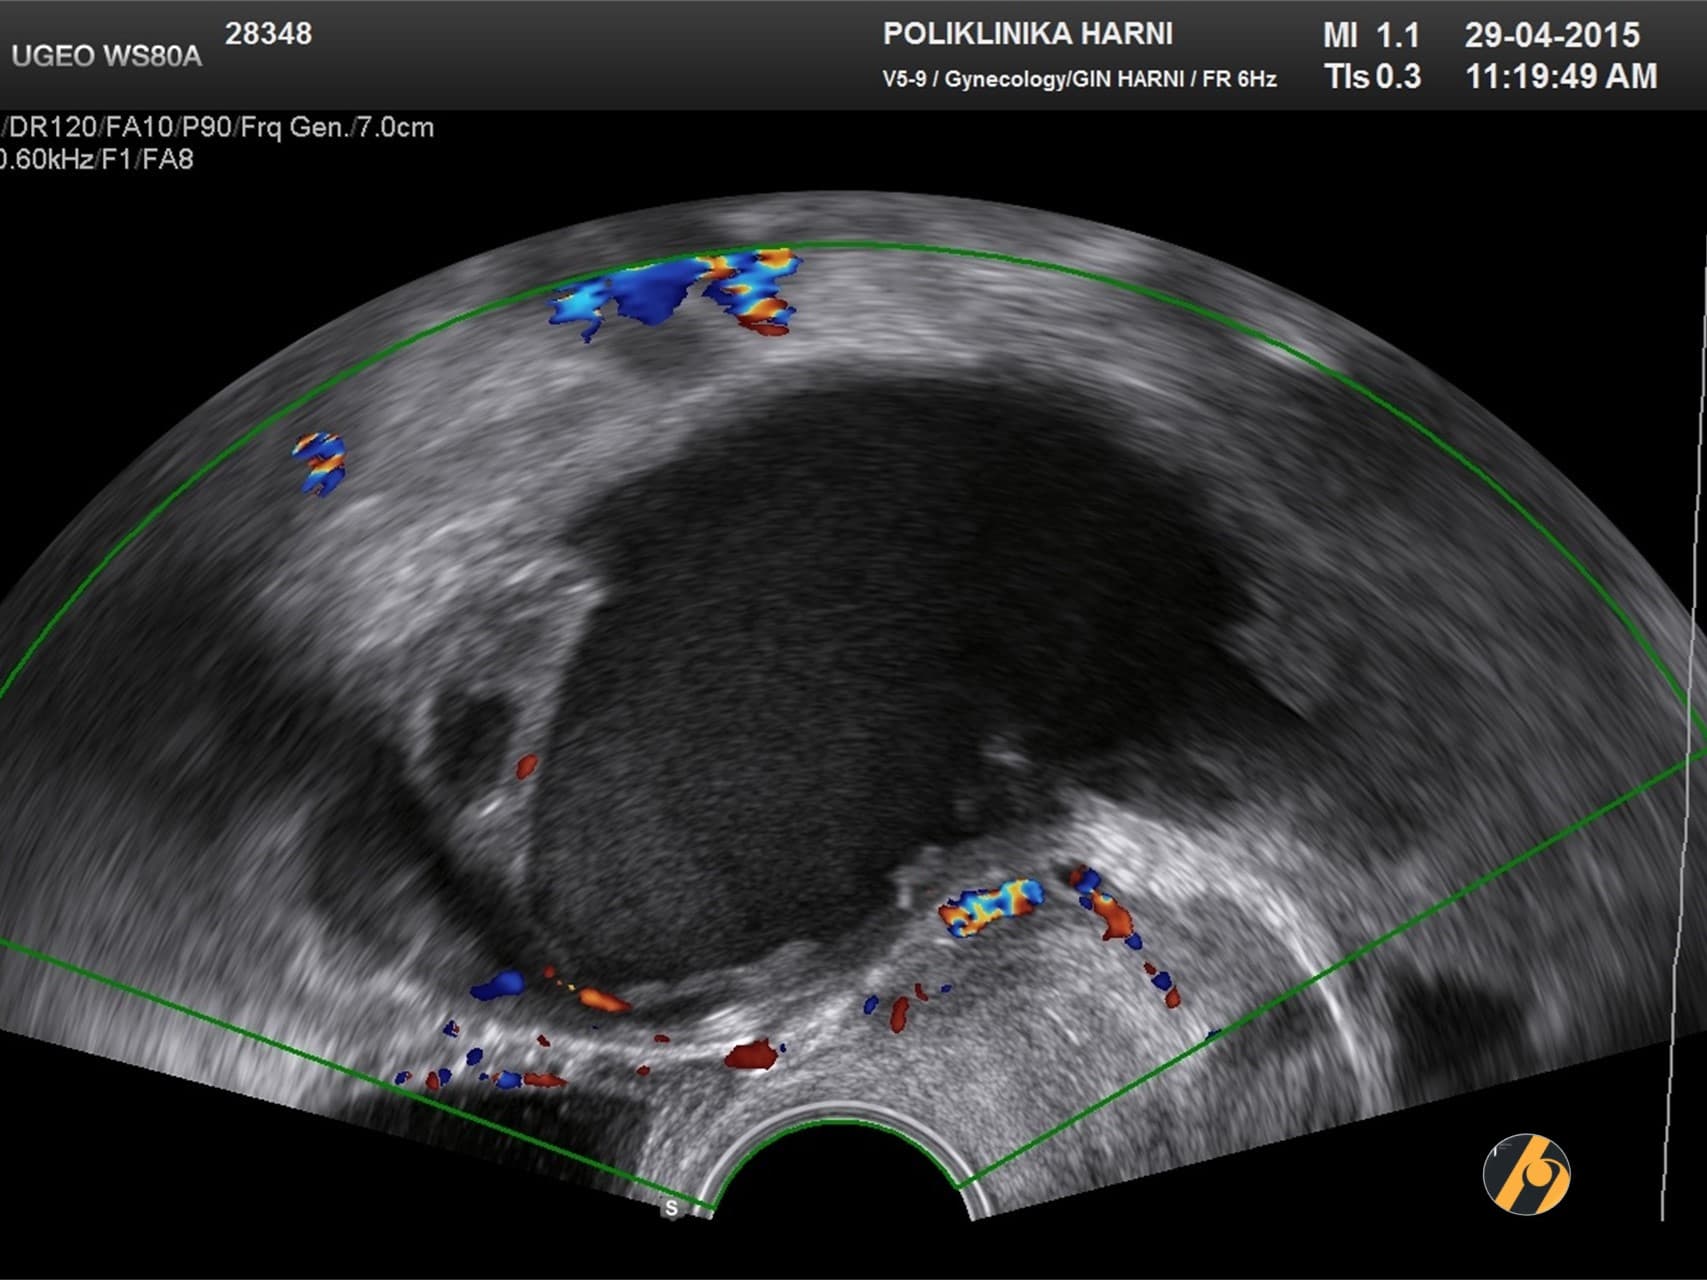

Premda su laparoskopija i patohistološka dijagnostika zlatni standard u dijagnostici endometrioze, u postavljanju dijagnoze od pomoći mogu biti i drugi manje invazivni postupci. Nažalost, ove tehnike kao što su transvaginalna sonografija i magnetska rezonancija nisu u stanju otkriti manje ili lezije koje su manje aktivne. Transvaginalna ultrazvučna dijagnostika učinkovito otkriva endometriotička žarišta čiji je promjer veći od 19 mm (¾ incha).